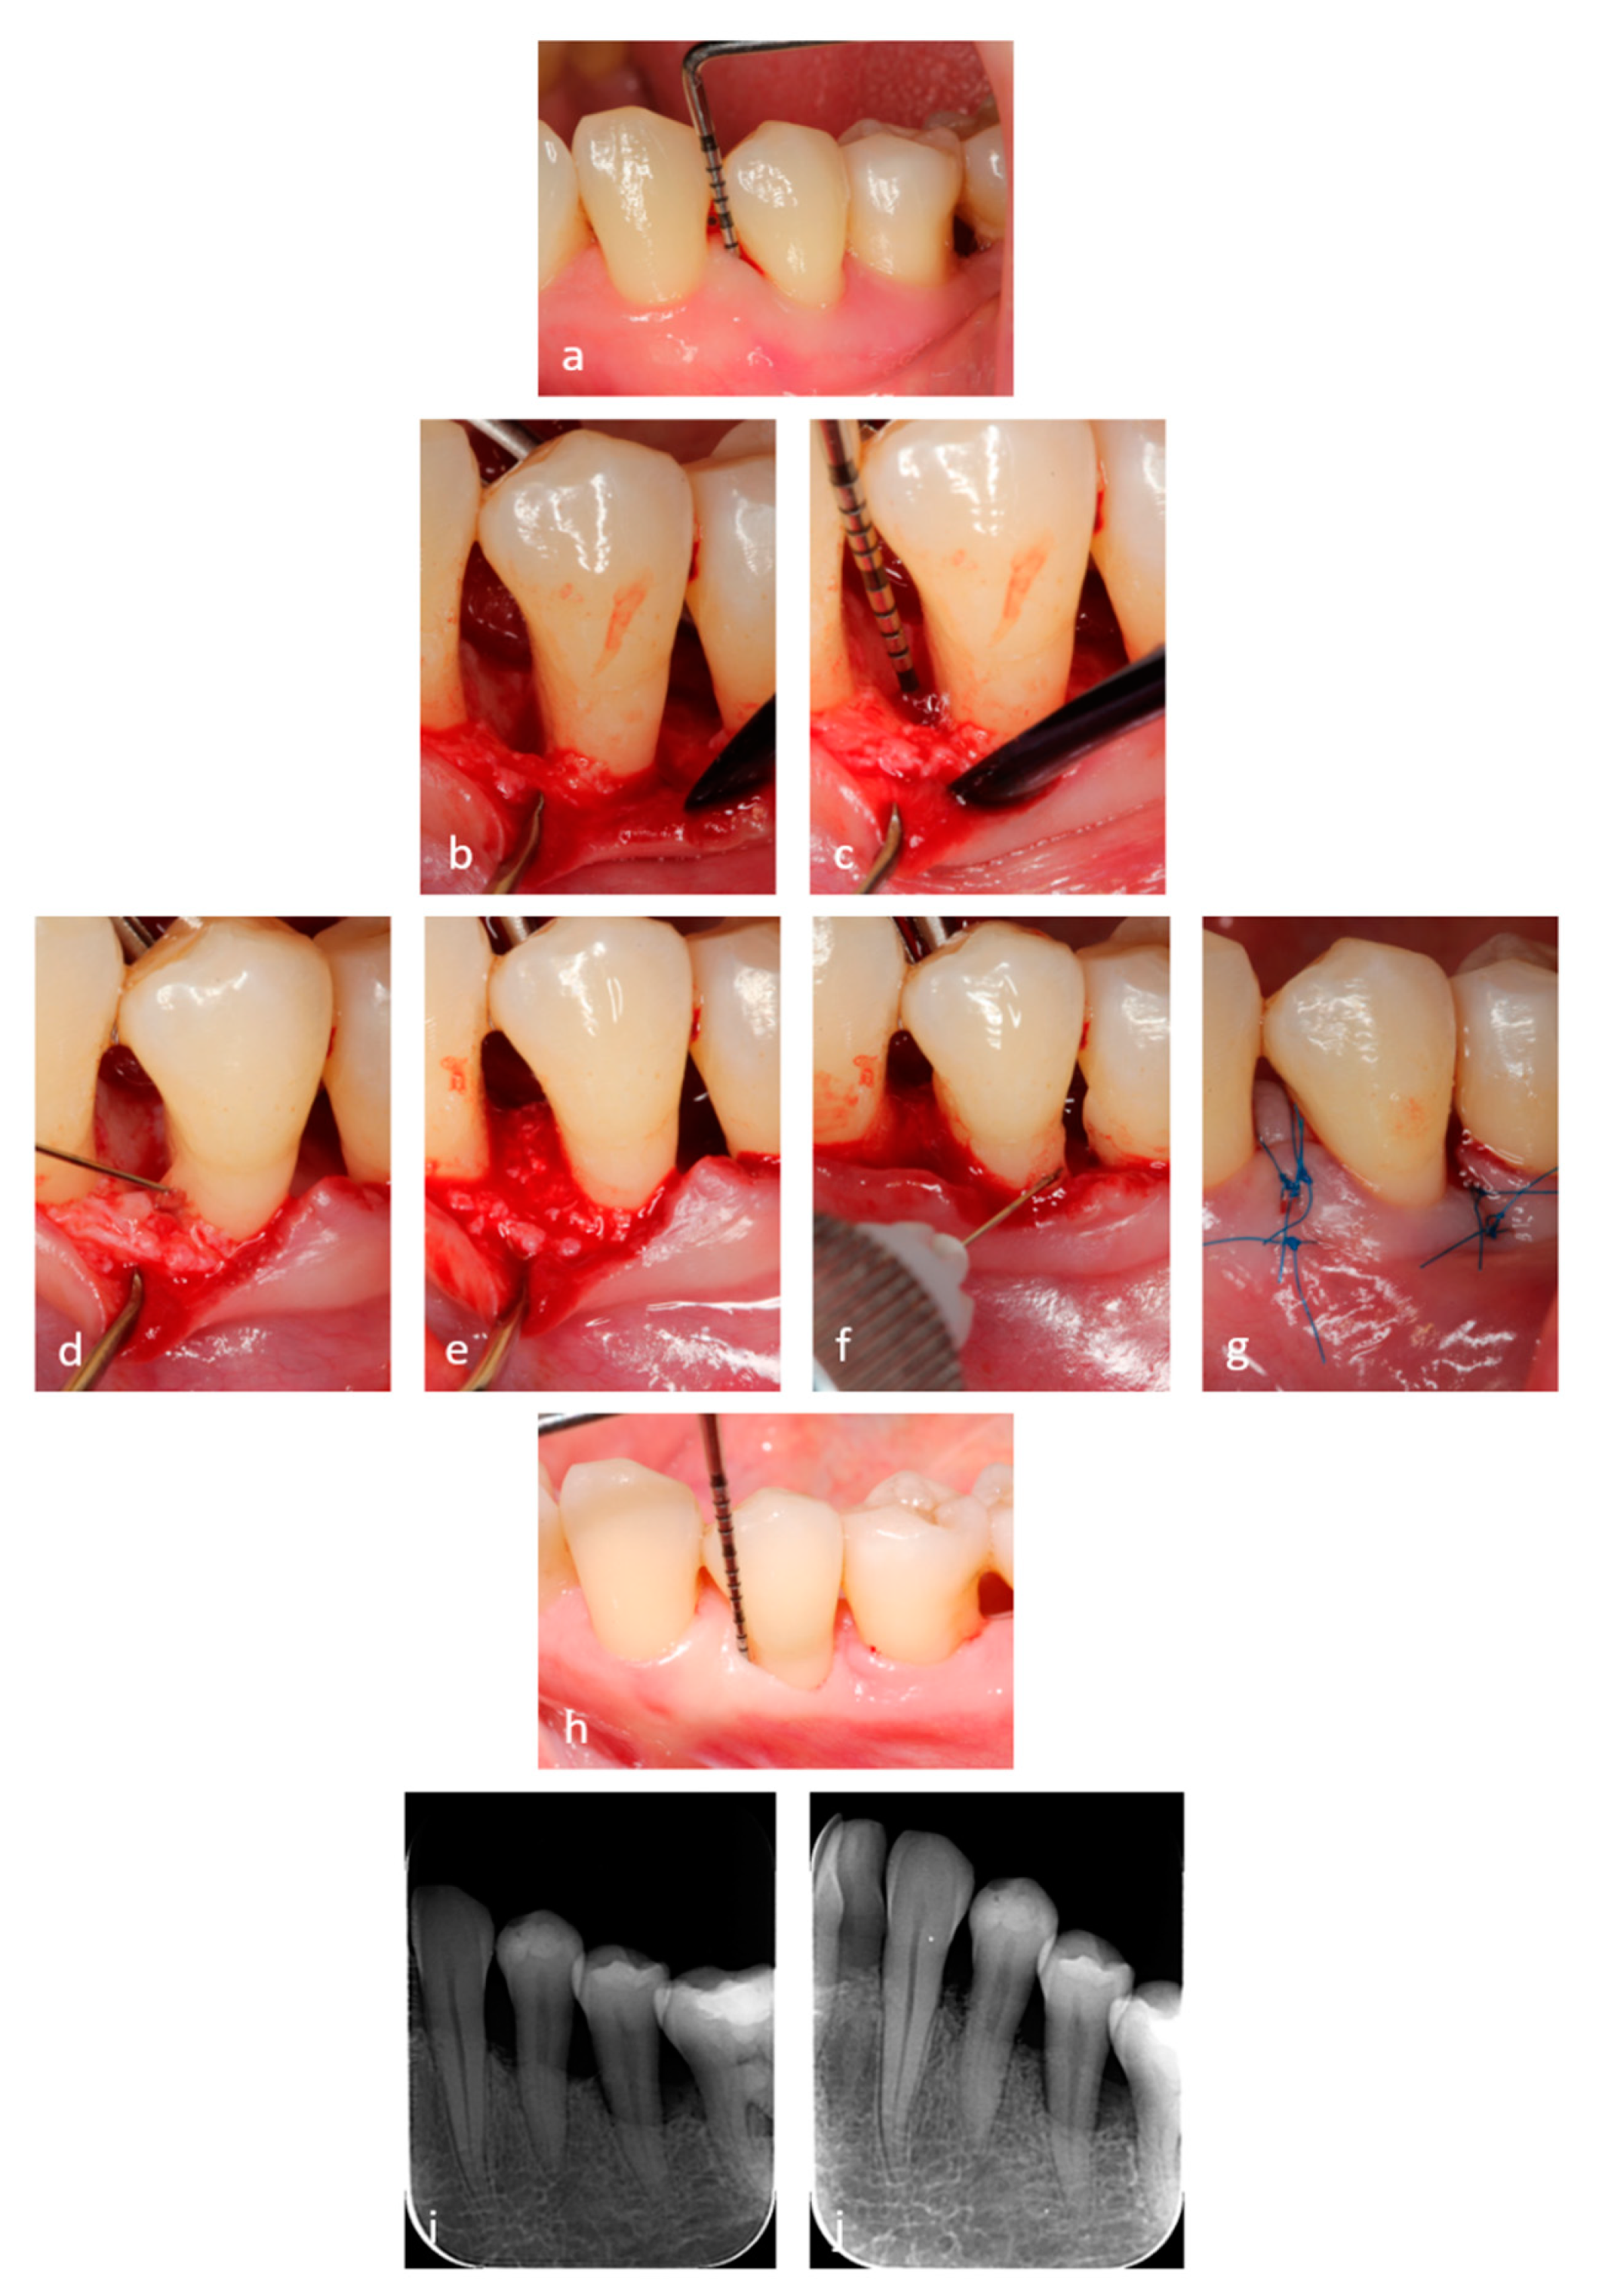

2.3. Surgical Procedures

2.4. Application of the Hyaluronic Acid (HA) and Xenograft